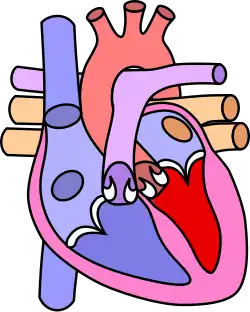

![]() | |

| Diagram of a healthy heart and one with tetralogy of Fallot | |

Four malformations

"Tetralogy" denotes four parts, here implying the syndrome's four anatomic defects.[2] This is not to be confused with the similarly named teratology, a field of medicine concerned with abnormal development and congenital malformations (including tetralogy of Fallot). Below are the four heart malformations that present together in tetralogy of Fallot:

| Right ventricular hypertrophy | The right ventricle is more muscular than normal, causing a characteristic boot-shaped (coeur-en-sabot) appearance as seen by chest X-ray. Due to the misarrangement of the external ventricular septum, the right ventricular wall increases in size to deal with the increased obstruction to the right outflow tract. This feature is now generally agreed to be a secondary anomaly, as the level of hypertrophy tends to increase with age.[45] |